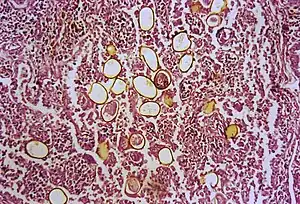

The first human case was seen in 1879 in Taiwan. An autopsy was done and adult trematodes were found in the lungs. The adult flukes have a reddish-brown in color with an ovoid shape. They have two muscular suckers, the first an oral sucker located anteriorly and the second a ventral sucker located mid-body. The adult flukes can live up to 20 years. The eggs are golden brown in color and are asymmetrically ovoid. They have a very thick shell. As seen above, these trematodes have a very complex life cycle with seven distinct phases involving intermediate hosts and humans.[16] These seven phases are outlined as follows: eggs reach fresh water where they develop into miracidia. These penetrate many species of aquatic snails (first intermediate host) where they go through three distinct stages: first sporocysts, then rediae, and finally cercariae, also referred to as the larvae. These larvae released into water and penetrate crabs, crayfish and other crustaceans (second intermediate host). The cercariae situate themselves into the gills, liver and muscles where they further develop into metacercariae. When the parasite-filled crustacean is eaten, the metacercariae hatch in the intestine. These young worms penetrate intestinal wall, peritoneum, the diaphragm and the pleura where they finally reach the lungs. Here they live in pairs, lay eggs that are coughed up in sputum to restart the cycle.[17]